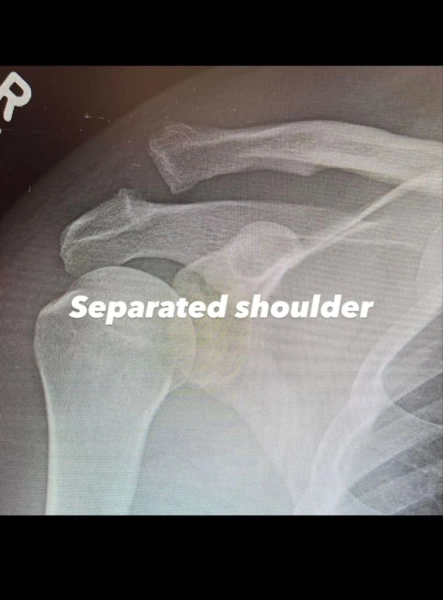

Як стало відомо, операція була викликана необхідністю внаслідок вивиху акроміально-ключичного з’єднання. Аби повернути плече у правильне положення, медикам довелось вдатися до оперативного втручання.

Окрім цього, актор оприлюднив рентгенівські знімки плеча до та після проведення операції. Ченнінг Татум не повідомив обставини отриманої травми, але запевнив, що сповнений рішучості здолати труднощі та цілковито відновитися.